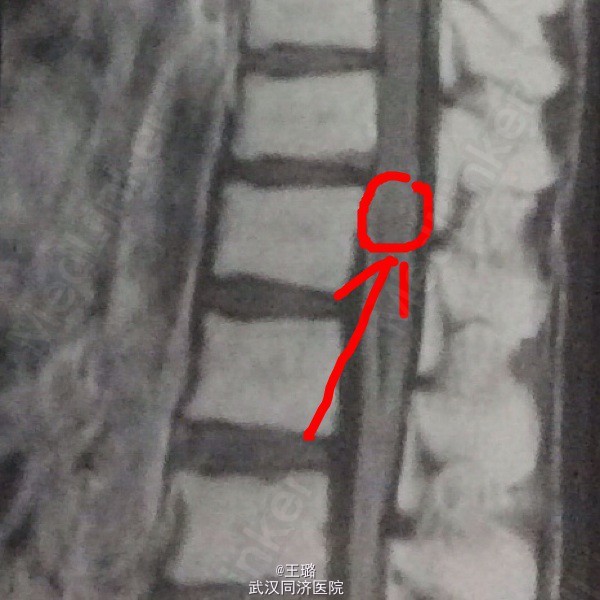

体格检查:体温38度,肺部未闻及干湿啰音,肢体肌力减低,神经反射弱,病理反射未引出。实验室检查:淋巴细胞增高,余正常。电解质、生化检查无异常。影像学检查:CT增强:病灶呈环形强化,壁厚薄较为均匀。MRI:腰段脊髓呈梭形增粗,其内见一类圆形病灶。

诊断:脊髓占位性病变待查 治疗:形脊髓腔切开切除占位性病灶,病检示:结核球,遂给予口服抗结核药物标准化治疗。一次药物鞘内注射。